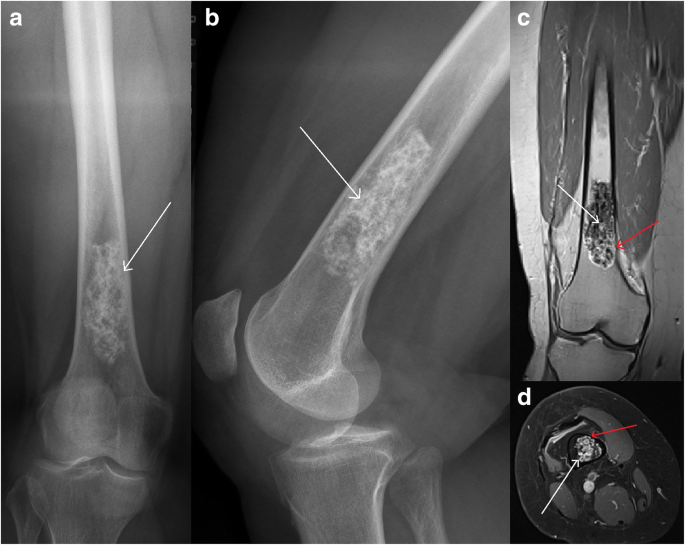

Enchondroma Femur

Enchondroma - OrthoInfo - AAOS An Enchondroma Incidentally Noticed in the Distal Femur Radiograph of a... | Download Scientific Diagram Femoral enchondroma | Radiology Case | Radiopaedia.org Fortunately, Enchondroma Lesions Are Rarely Malignant Enchondroma - distal femur | Radiology Case | Radiopaedia.org UW MSK Resident Projects : Enchondromas and Related Disorders | Enchondroma Femur